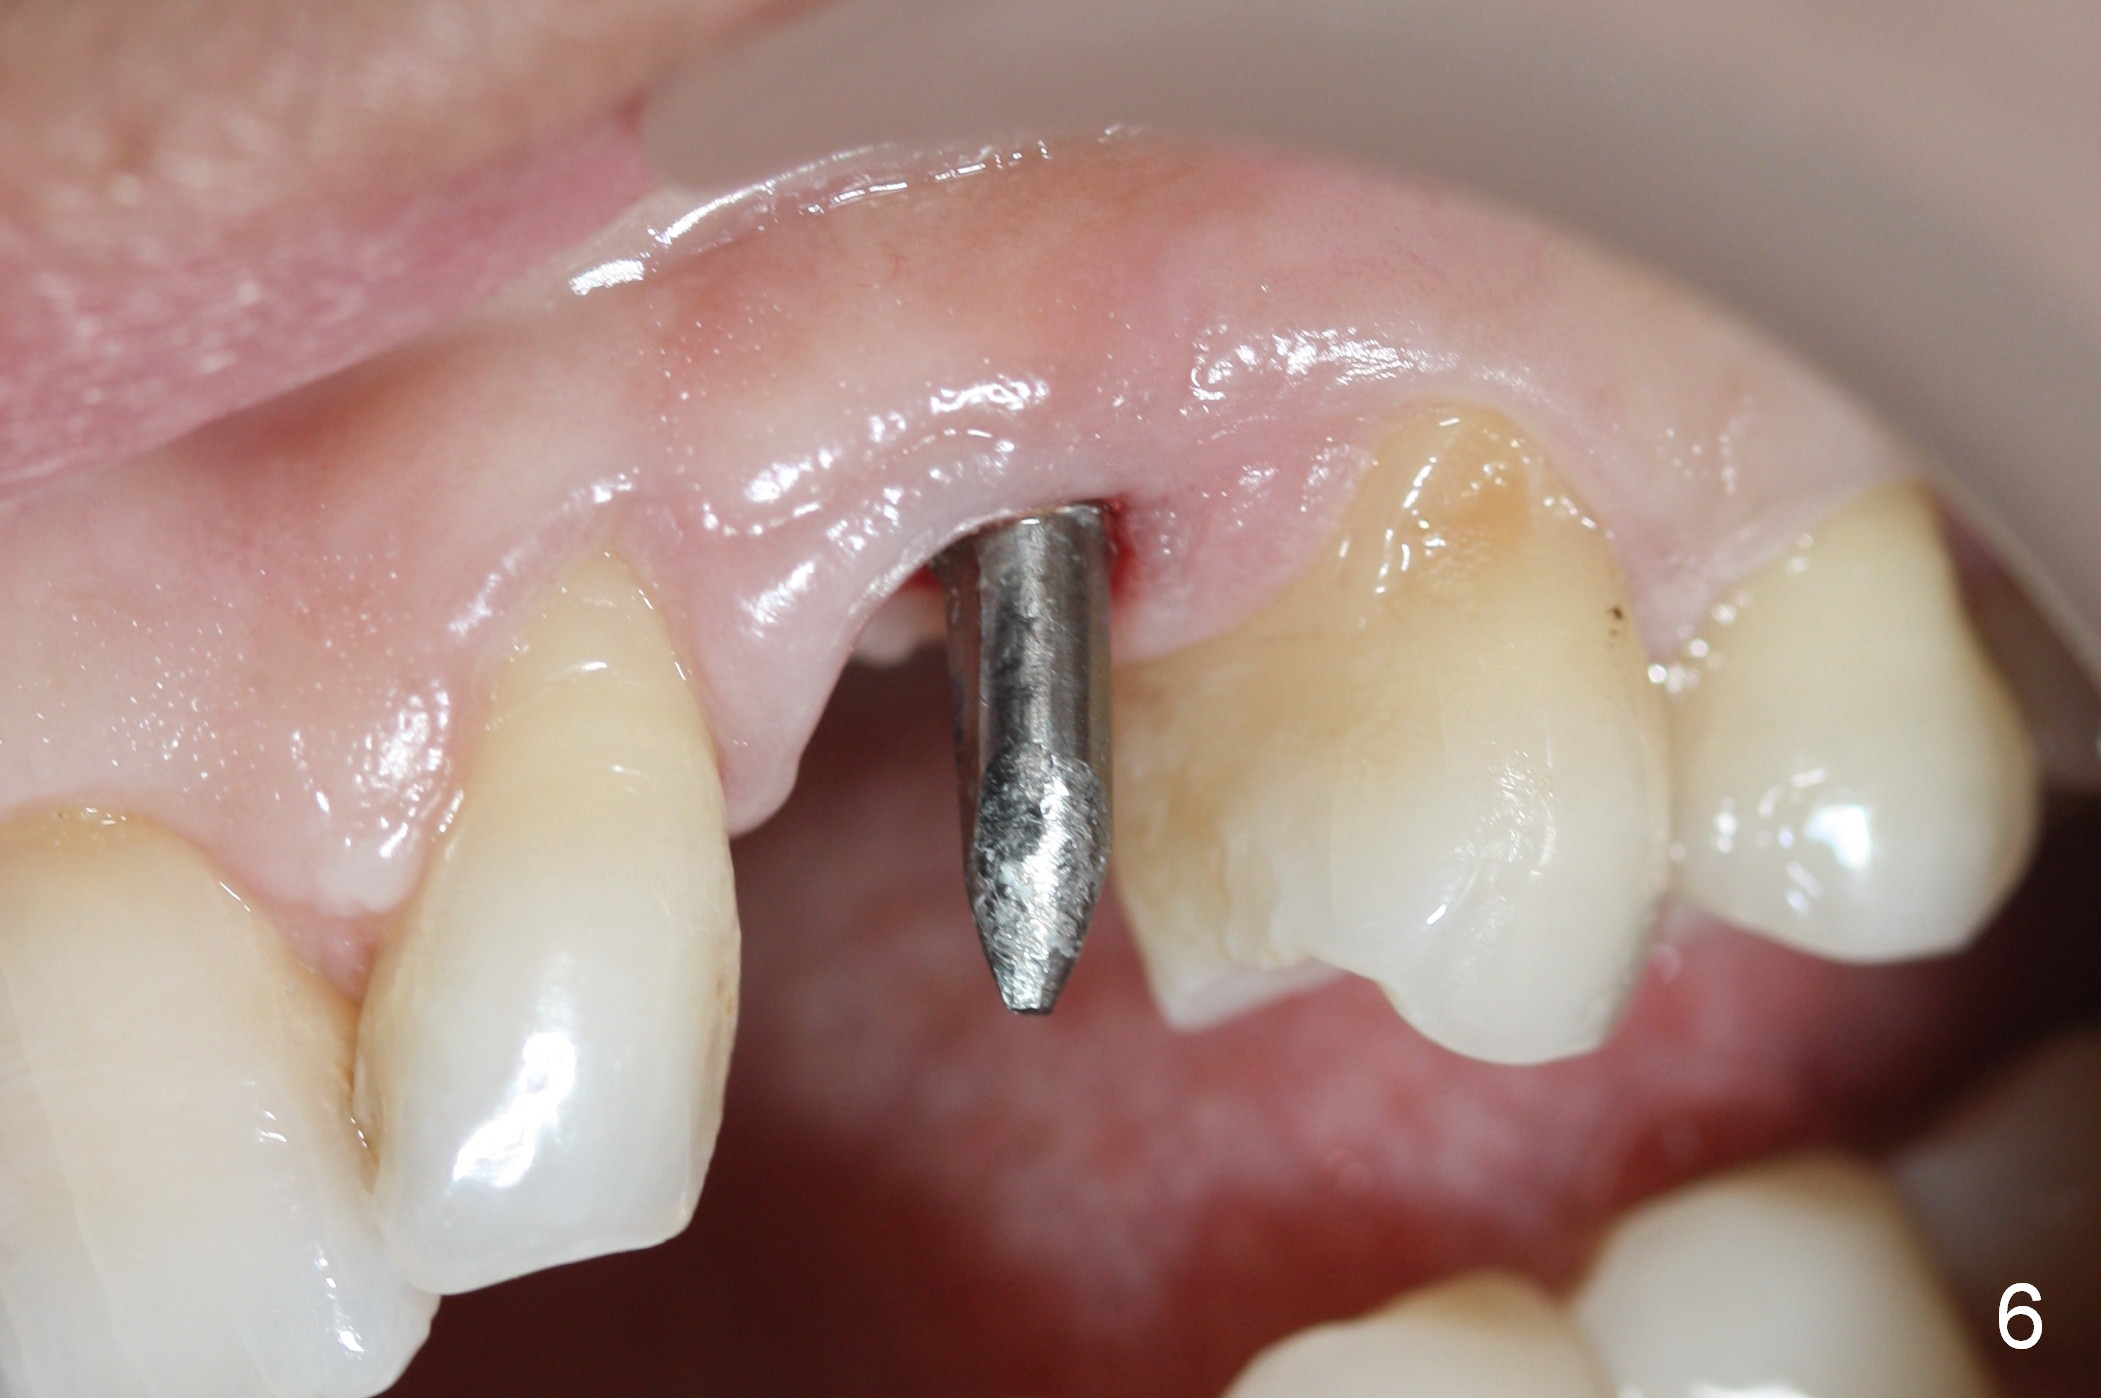

Eight months postop, the patient returns for #11 restoration. She reports no problem at #11, while there is light tenderness with a 2-piece implant (4.5x20 mm) at #6 at night (Fig.10, a portion of panoramic X-ray). Clinical exam reveals no abnormality at #6. Although the implant at #11 is buccally placed, there is no buccal plate atrophy (Fig.6,7). In fact the 20 mm 1-piece implant is placed in the bone (septum) between the nasal cavity (Fig.10 pink dashed line; Fig.13 (CBCT (52 year-old lady) N) and the maxillary sinus (yellow dashed line, S). In fact the apparent nasal floor indicated as arrowheads in Fig.2 and 10 is the horizontal plate of the palatine bone (hard palate)! Therefore there is no nasal floor perforation in this case. A long implant is indicated in the upper canine.

The main reason for the failure of this case is buccal placement of the implant (Fig.11 A: abutment). Every time an implant is placed at the upper anterior, make sure that palatal placement is done (Fig.12 *). The most critical step is the 1st pilot drill. If the position is not ideal, use a Lindemann bur for adjustment. Check repeatedly. If the implant starts to be deviated buccally, remove the implant, use the Lindemann bur to remove more of the palatal bone and place the implant palatally.